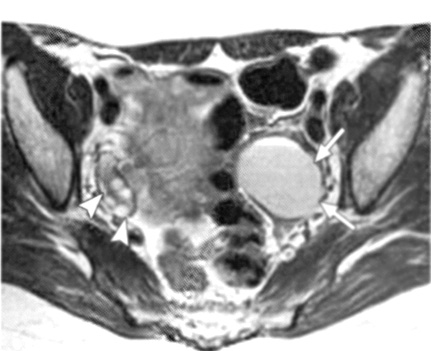

Εικόνα 2. Ωοθηκικά ενδομητριώματα. Εγκάρσιες Τ1(Α) και Τ2(Β) εικόνες μαγνητικής τομογραφίας αμφοτερόπλευρων ωοθηκικών ενδομητριωμάτων. Υψηλής έντασης σήμα και στις δύο ακολουθίες (βέλη), χαρακτηριστικό των ενδομητριωμάτων. Χαμηλής έντασης σήμα μεταξύ των ωοθηκών (κεφαλή βέλους) και του σιγμοειδούς (S), που αντιστοιχεί σε ινώδεις συμφύσεις. *=ωοθυλάκιο

H μαγνητική τομογραφία (MRI) έχει αποδειχθεί ως ένα χρήσιμο μη επεμβατικό διαγνωστικό μέσο της ενδομητρίωσης. H μαγνητική τομογραφία υπερέχει της υπερηχογραφίας στην ενδομητρίωση του περιτοναίου, η οποία εμφανίζεται ως πολλαπλά μικρά οζίδια, γιατί μπορεί να ανιχνεύσει την ύπαρξη ενδομητριωσικών εμφυτεύσεων στις Τ1 ακολουθίες με ευαισθησία 11-27% και με σήμα το οποίο ποικίλει σε ένταση ανάλογα με την ενεργό δραστηριότητα και τη χρονική διάρκεια της βλάβης. Στις Τ2 ακολουθίες οι εμφυτεύσεις εμφανίζονται ως μάζες χαμηλού σήματος λόγω της αντιδραστικής ίνωσης που περιβάλλει τις μικρές συλλογές ενδομητριωσικού υλικού, αν και κάποιες φορές στο εσωτερικό των εμφυτεύσεων μπορεί να υπάρχει υψηλής έντασης σήμα λόγω της κυκλικής αιμορραγίας (εικόνα 2). Όταν όμως οι λήψεις της μαγνητικής τομογραφίας λαμβάνονται με καταστολή του λίπους, βελτιώνεται η ανίχνευση των ενδομητριωσικών εμφυτεύσεων στο περιτόναιο, αυξάνοντας την ευαισθησία της μεθόδου στο 47-61% και την ειδικότητα στο 87-97%.

Επιπλέον, στη μαγνητική τομογραφία οι συμφύσεις εμφανίζονται ως χαμηλής έντασης σήματος νηματοειδείς σχηματισμοί, οι οποίοι καθιστούν ασαφείς τις διαχωριστικές επιφάνειες δύο παρακείμενων οργάνων και μπορούν ενίοτε να προσλαμβάνουν σκιαστικό, χωρίς ωστόσο να αυξάνουν την ευαισθησία ή την ειδικότητα της μαγνητικής τομογραφίας. Σύμφωνα με μελέτη των Katayama και συν. εκτιμήθηκε η αξία της μαγνητικής τομογραφίας στην εκτίμηση των πυελικών συμφύσεων χρησιμοποιώντας μια ειδική τεχνική και διαπιστώθηκε πως η ευαισθησία και η ειδικότητα της μεθόδου είναι 72.5% και 87.4% αντίστοιχα. Η οπίσθια κλίση και καθήλωση της μήτρας στον δουγλάσειο, η προσκόλληση των ωοθηκών μεταξύ τους και στην οπίσθια επιφάνεια της μήτρας, η γωνίωση των εντερικών ελίκων, η ανύψωση των οπίσθιων κολπικών θόλων, η εγκυστωμένη συλλογή υγρού και η παρουσία υδροσαλπίγγων αποτελούν έμμεσα ευρήματα, ενδεικτικά συμφύσεων (εικόνα 3).(15,16)

Η μαγνητική τομογραφία έχει αποδειχθεί χρήσιμη στη διάγνωση των ενδομητριωμάτων, με ευαισθησία και ειδικότητα συγκρίσιμη, και σύμφωνα με κάποιους ερευνητές, μεγαλύτερη της διακολπικής υπερηχογραφίας, αλλά σαφώς και με μεγαλύτερο κόστος ως εξέταση. Συγκεκριμένα ο Takahashi διαπίστωσε πως τόσο η κλασική, όσο και η μαγνητική τομογραφία με καταστολή του λίπους ανιχνεύει όλα σχεδόν τα ενδομητριώματα με διάμετρο μεγαλύτερη των 10 χιλιοστών.(17) Ακόμη η νόσος μπορεί να βρίσκεται σε αρχικό στάδιο, όταν η μαγνητική τομογραφία ανιχνεύει βλάβες μικρότερες των 6 χιλιοστών, ενώ βλάβες μεγαλύτερες των 15 χιλιοστών συσχετίζονται με προχωρημένο στάδιο.(18) Στην κλασική μαγνητική τομογραφία τα ενδομητριώματα εμφανίζονται ως πολλαπλές, ομοιογενείς, υψηλού σήματος μάζες στις Τ1 ακολουθίες και με χαμηλής έντασης σήμα στις Τ2 ακολουθίες ως «σκιά» λόγω της αποδόμησης των προϊόντων του αίματος και της δημιουργίας αιμοσιδηρίνης. Όμως σε περίπτωση πρόσφατου ενεργού ενδομητριώματος η παρουσία αίματος και στις δύο, Τ1 και Τ2, ακολουθίες θα εκδηλώνεται ως υψηλής έντασης σήμα, γεγονός που καθιστά δύσκολη τη διαφοροδιάγνωση από τις αιμορραγικές κύστεις των ωοθηκών. Επίσης, το παχύ ινώδες τοίχωμα της ενδομητριωσικής κύστης εμφανίζεται ως χαμηλής έντασης σήμα στις Τ2 ακολουθίες, με πρώιμη πρόσληψη του σκιαστικού εξαιτίας της ύπαρξης αγγείωσης και μακροφάγων με αιμοσιδηρίνη.